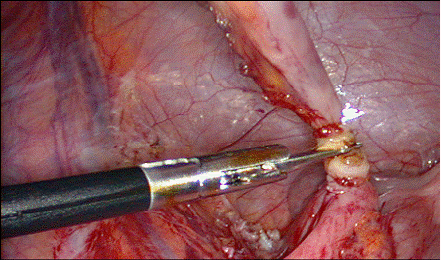

l daca mezoul este vizibil, nu este grasos sau inflamat si artera apendiculara se poate identifica, se creeaza o fereastra in mezou, deasupra ei si se aplica un clip pe vasele apendiculare, apoi se sectioneaza mezoapendicele; prin aceasta fereastra se poate introduce un fir neresorbabil pentru artera apendiculara, care se innoada intra - si extracorporeal; acest fir poate fi trecut si cu ajutorul unui ac;

Fig. 19 Aplicarea

clipurilor pe mezoapendice